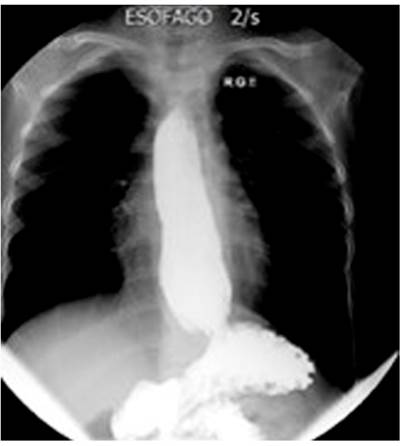

Por la disfagia reciente, se indicaron diversos estudios. En primer lugar, se realizó una radiografía de las vías digestivas altas, la cual evidenció un aumento del diámetro del esófago, reflujo severo y la alteración del peristaltismo con ondas terciarias (Figura 2). Además, se efectuó una EGD, que mostró una esofagitis de grado D (según la clasificación de los Ángeles), un pólipo hiperplásico, una hernia hiatal pequeña, antro con gastritis folicular y un duodeno normal (Figura 3).